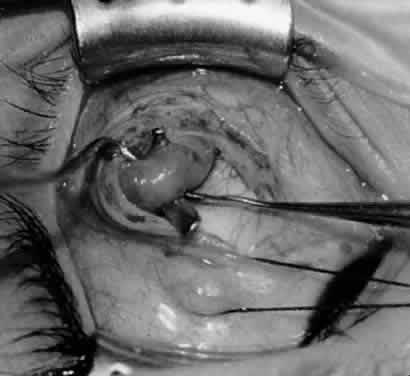

Fig. 21. A hemostat is placed adjacent to the insertion of the right inferior oblique muscle.

Fig. 22. An Aebli scissor is used to section the inferior oblique muscle from the globe.

Fig. 23. The inferior oblique muscle is drawn into the operative field with a hemostat. This step may be used for the recession procedure if the surgeon is concerned about the placement of the 6-0 Vicryl suture while the muscle is attached to the globe in the proximity of the macula. The recession sequence would follow after the placement of the suture while the muscle is grasped in the hemostat.

Fig. 24. The eyelid speculum is removed and a Desmarres lid retractor is placed inferiorly. The inferior oblique muscle is drawn superiorly and nasally. The fusiform expansion of the inferior oblique muscle is evident on the posterior border, where the nerve to the inferior oblique muscle and artery and vein enter the inferior oblique muscle. The Stevens muscle hook is used to hook the neurovascular bundle.

Fig. 25. The hook is advanced further for identification of the neurovascular bundle on the inferior oblique muscle.

Fig. 26. Cautery is applied to sever the neurovascular bundle, and a sponge is used to protect the sclera and lids from cautery.

Fig. 27. As the neurovascular bundle is severed completely, the inferior oblique muscle will be released of the normal tension provided by the neurovascular bundle on the posterior border of the inferior oblique muscle.

Fig. 28. The inferior oblique muscle is drawn further into the operative field, and a 3-0 Vicryl suture ligature is applied about the belly of the muscle.

Fig. 29. Cautery is used to sever the inferior oblique muscle and to provide hemostasis.

Fig. 30. The stump of muscle is placed through the Tenon's capsule opening. The surgeon must apply sufficient cautery to prevent postoperative bleeding.

Fig. 31. The inferior oblique muscle stump is visible at the opening in the Tenon's capsule before closure with 6-0 or 7-0 Vicryl suture. The S-28 half-circle curved needle is preferred to the S-29 needle, which has a 3–8-circle curve.

Fig. 32. The Tenon's capsule opening is closed with 6-0 or 7-0 Vicryl suture to place the inferior oblique muscle entirely outside Tenon's capsule.

The denervation procedure (Figs. 2132) allows the inferior oblique muscle to be released further into the operative field once the nerve has been sectioned (see Figs. 26 and 27). A 3-0 Vicryl suture ligature is placed around the inferior oblique muscle (see Fig. 28) as close to the Tenon's capsule penetration as possible. The inferior oblique is sectioned by cautery (see Fig. 29), just distal to the suture ligature. The cauterized stump is pushed through the opening in the Tenon's capsule (see Figs. 30 and 31) and a 6-0 or 7-0 Vicryl suture is used to close the opening, with either a running or a purse-string suture (see Fig. 32). The purse-string suture can be preplaced before the inferior oblique muscle is sectioned and closed after the muscle is sectioned. The advantage of the denervation and extirpation procedure is its ability to permanently correct 4+ overaction of the inferior oblique.10,18 In addition, it is the best operative procedure to eliminate recurring inferior oblique overaction after disinsertion, myectomy, or recession.10 Disadvantages include permanent underaction of the inferior oblique muscle in some patients. Pupil dilation can occur but the dilation usually is transient, clearing in 3 to 6 months.10,18